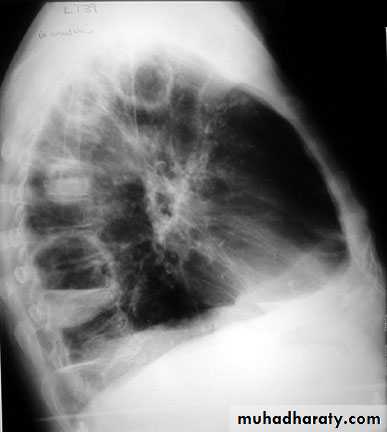

Lateral view position